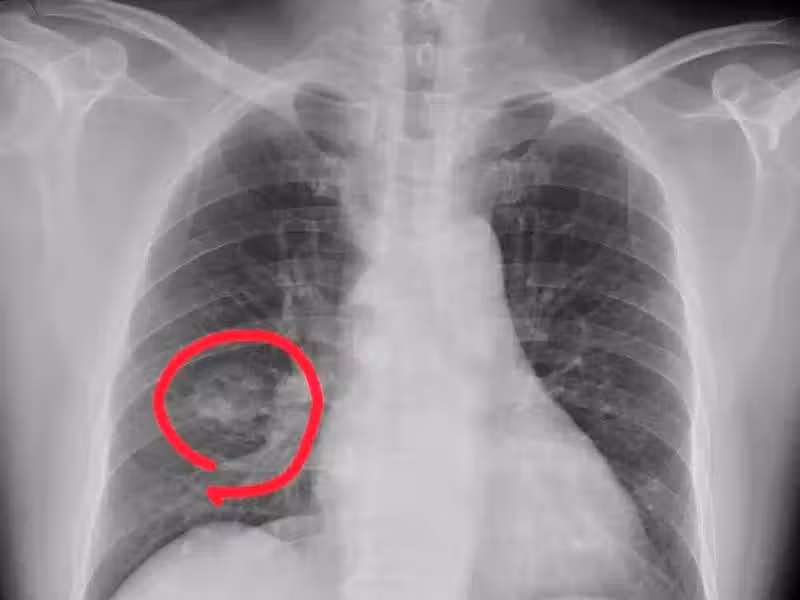

手腳出現 4 種異常,可能是得肺癌了,千萬不要大意

肺癌來臨並非無聲無息,提醒:手腳出現 4 種異常,可能是肺癌到來,不要大意!

1. 手指變粗

一般情況下手指變粗很可能是肺癌的信號,尤其是長期吸菸的男性朋友,要特別警惕杵狀指,也就是手指末端變粗,增生,膨大,同時還會伴有咳血、刺激性乾咳、胸痛等癥狀。